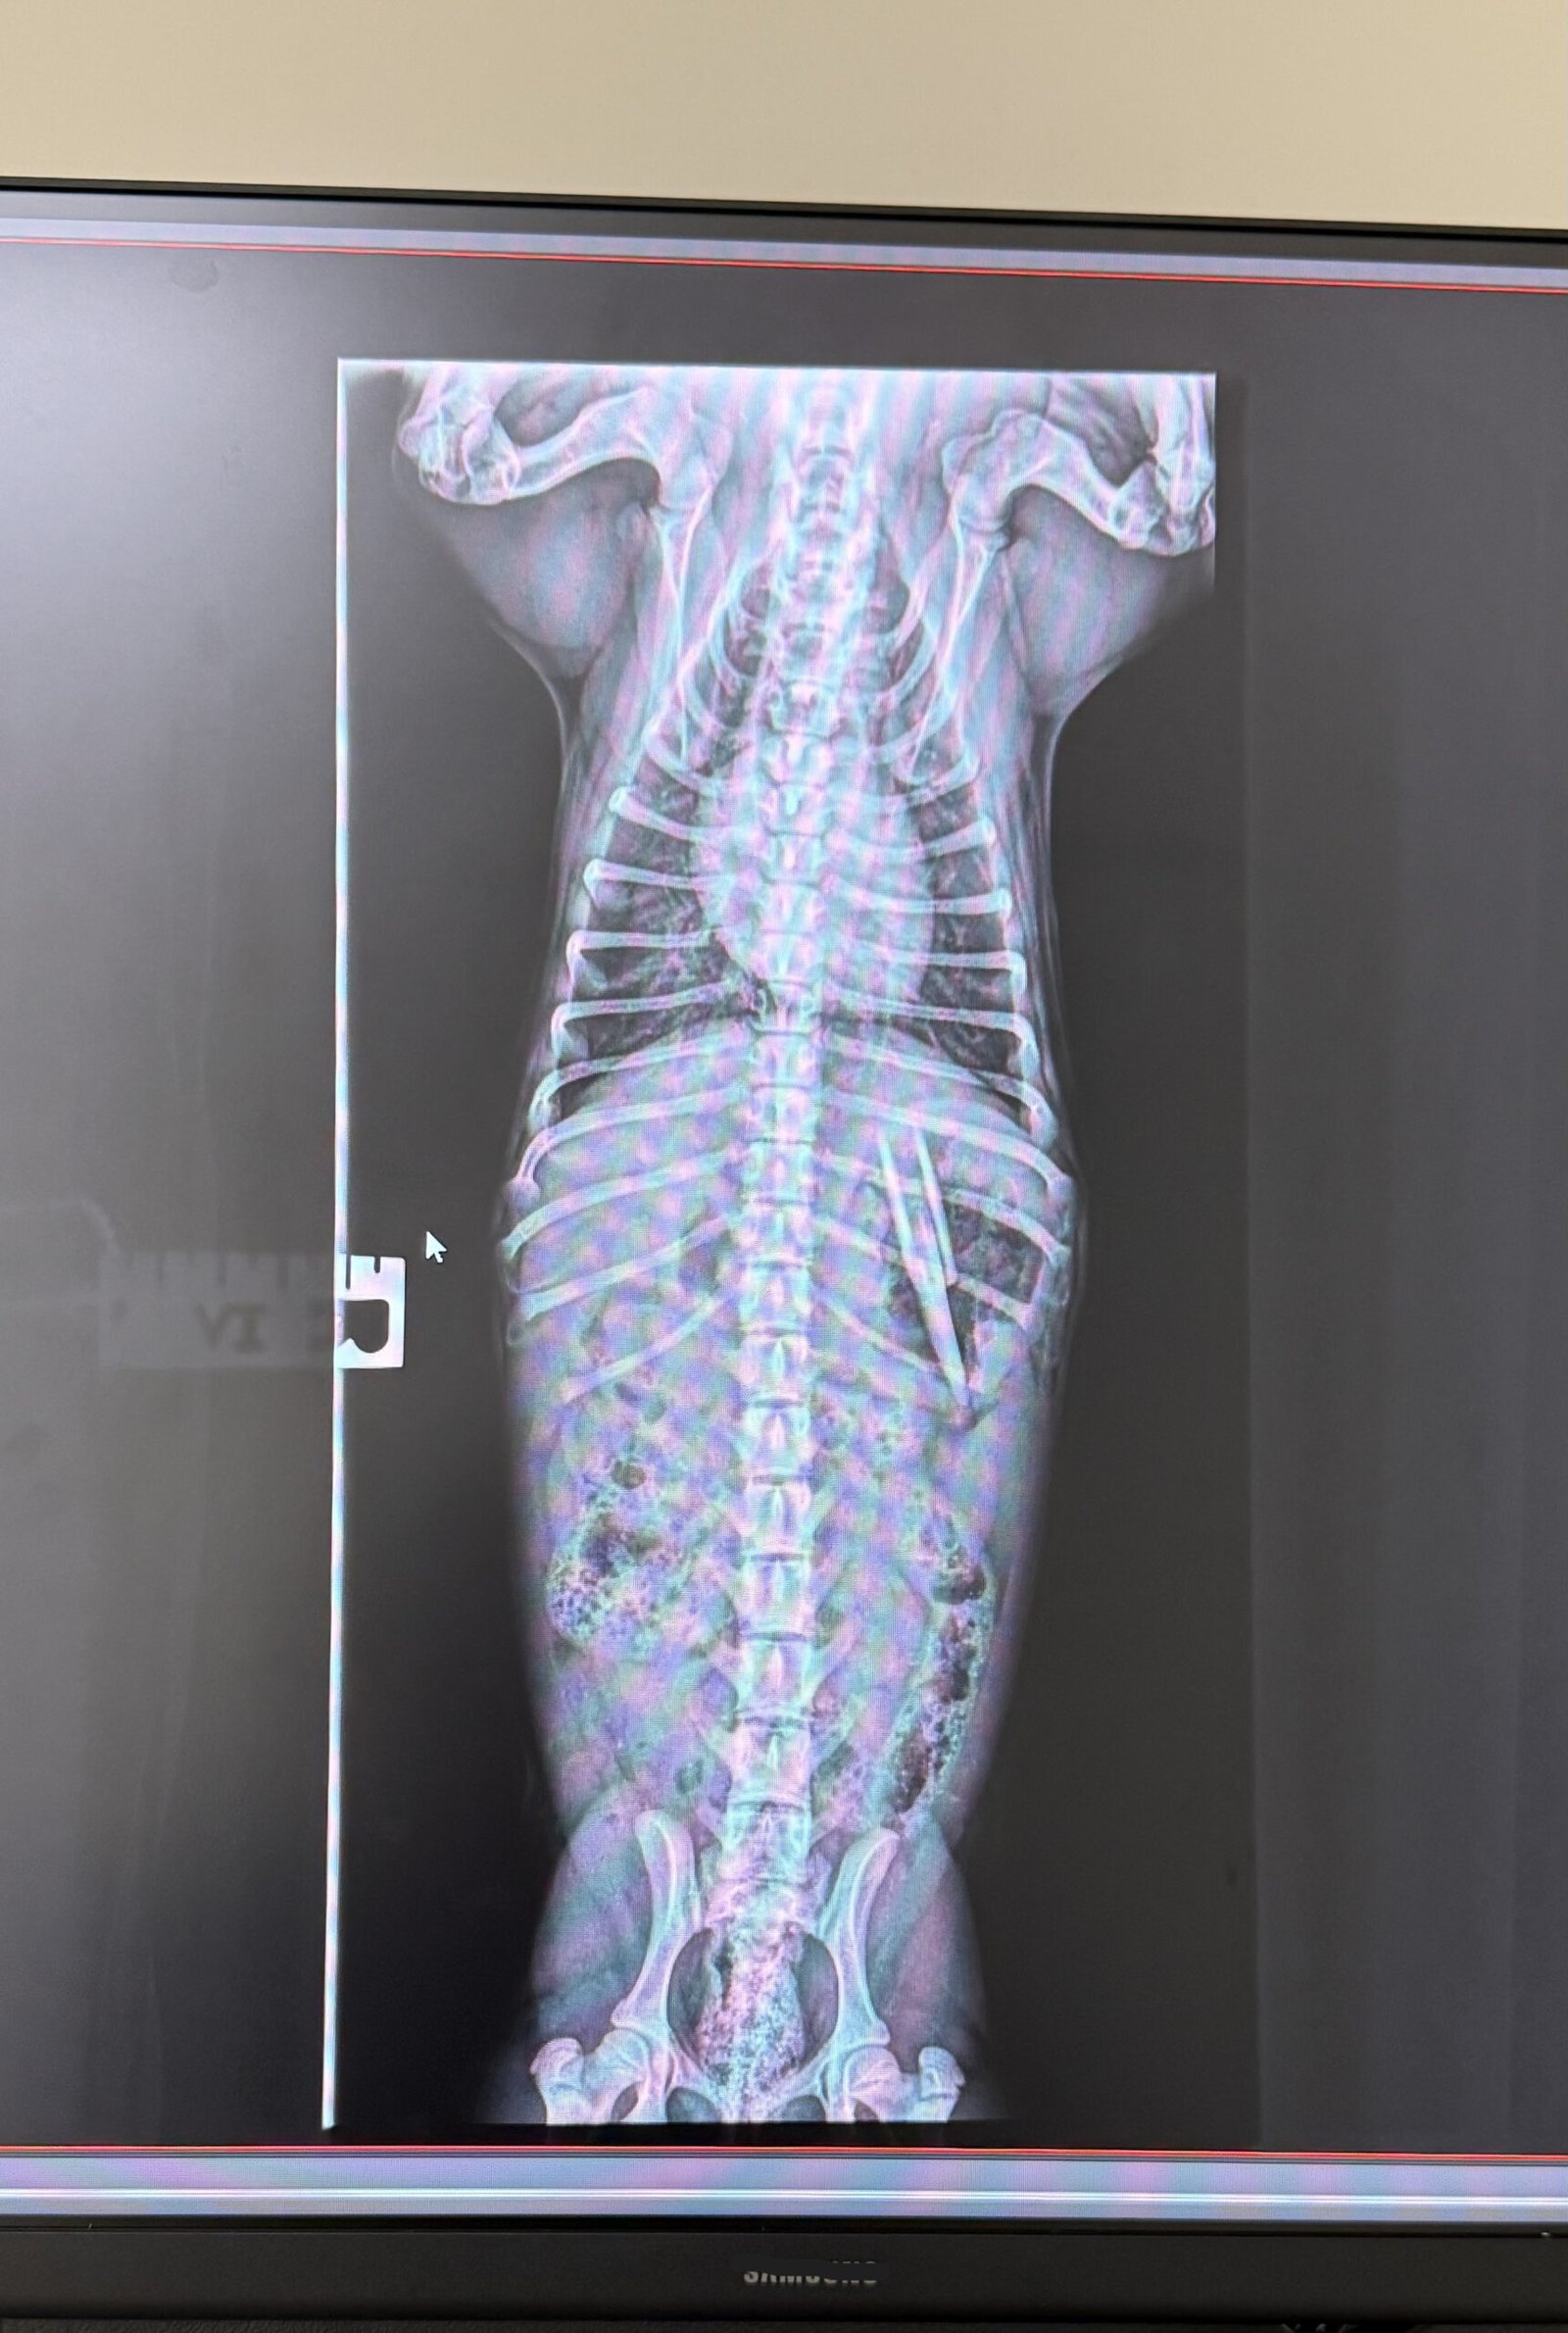

Meet this little cutie Remi. She is a 4 month old bundle of joy, but don’t let that foul you. She has a little rebellious side. Mom noticed she was playing with a spatula, first thing to do is grab the handle-as everyone would- but she decided to chomp her teeth down and as mom pulled the top of the spatula stayed in Remi’s mouth and of course as you should, she swallowed it. She came down and we induced vomiting, all that showed up was kibble and cheese, radiographs were taken and there we go, you can see the spatula.